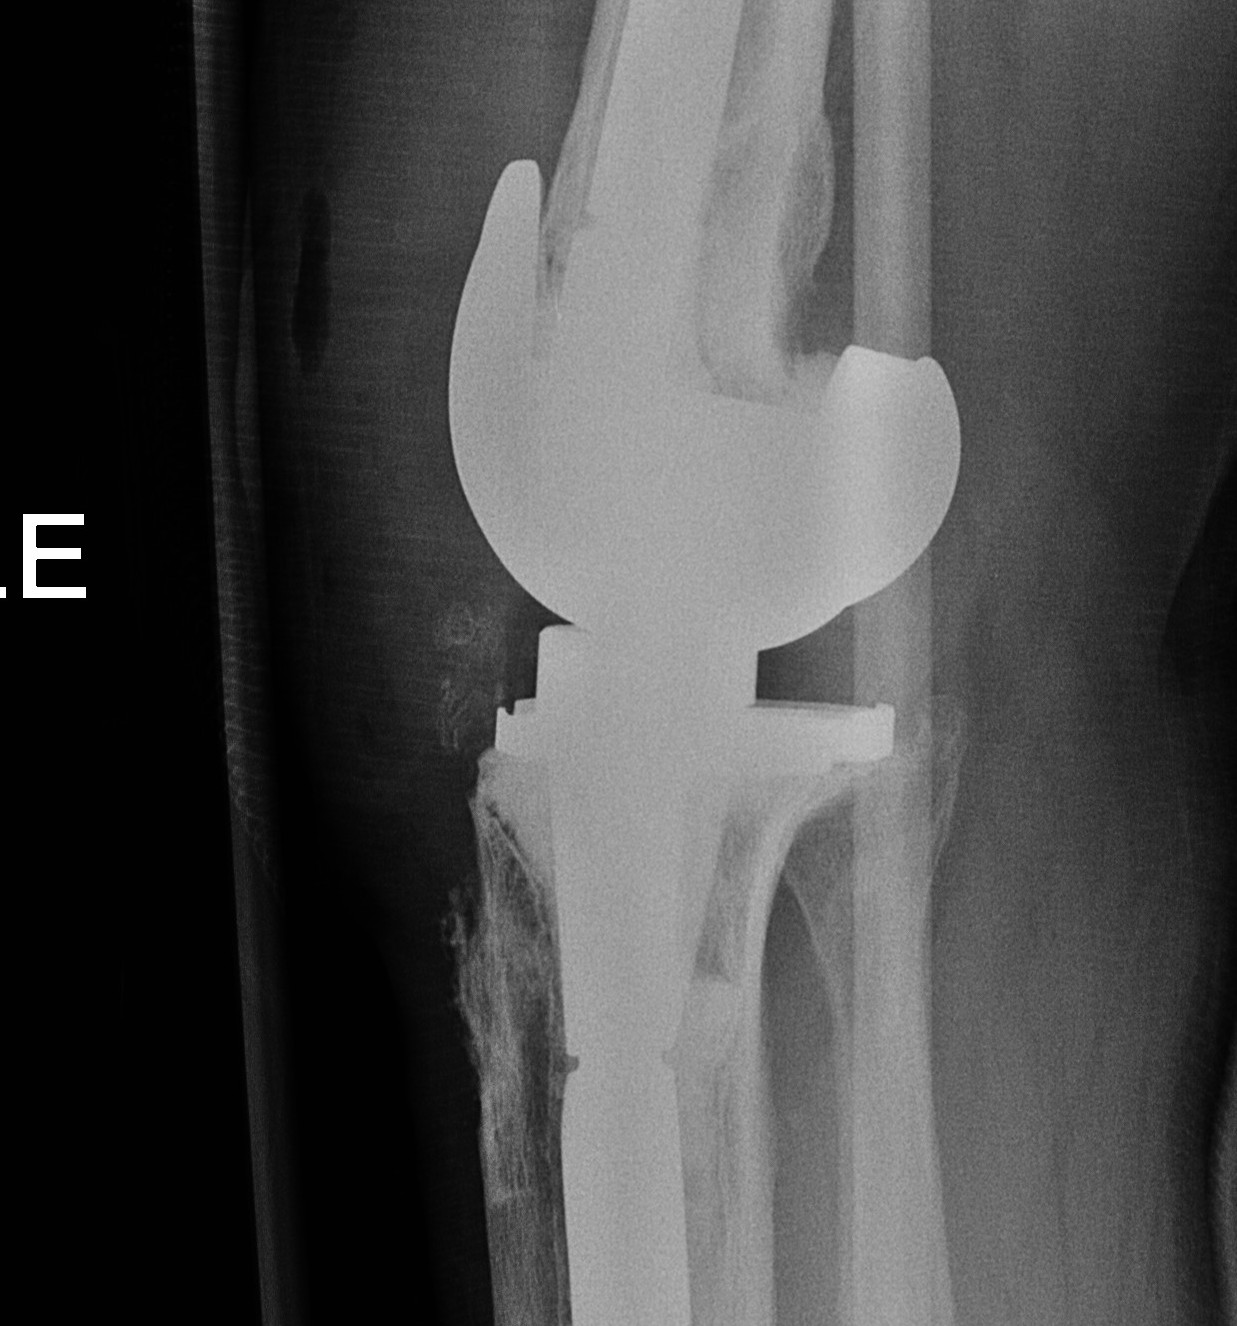

Distal femoral Cut

Distal cutting block on stem

- want to freshen surfaces minimally

- 1-2 mm off distal surface only

- consider distal femoral augments

- wait to trial extension gap to decide distal femoral augments

AP sizing

Posterior femoral condyles frequently deficient

- require augment posteriorly

- use anatomically sized femoral component

- template from other knee or use previous size from primary

- add augments posteriorly as

May need offset so femoral component sits on IM stem

Rotation

Trans-epicondylar axis most reliable

- posterior femoral condyles may be more deficient laterally than medially

- set correct rotation

- freshen AP and chamfer cuts